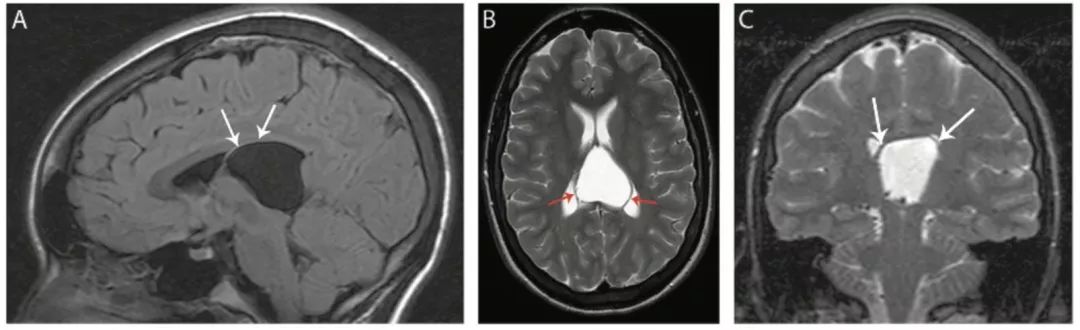

图14 中间帆腔

矢状位FLAIR (A)、轴位T2WI像(B)和冠状位T2WI像(C)显示了一个明显的中间帆腔,伴穹窿上部移位(箭头)。